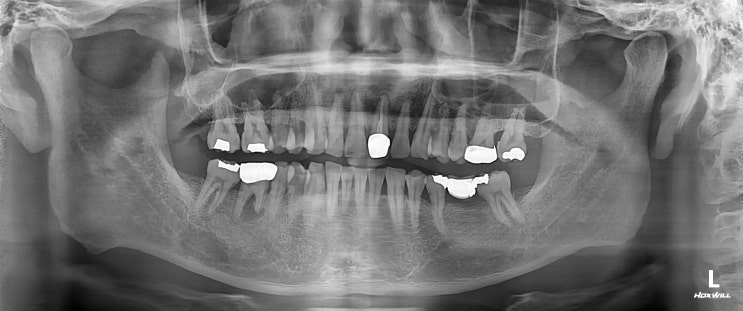

안녕하세요 수서역치과 문정도 치과 수서서울삼성치과 원장 이재현입니다 오늘은 신경치료 후 회복한 환자...